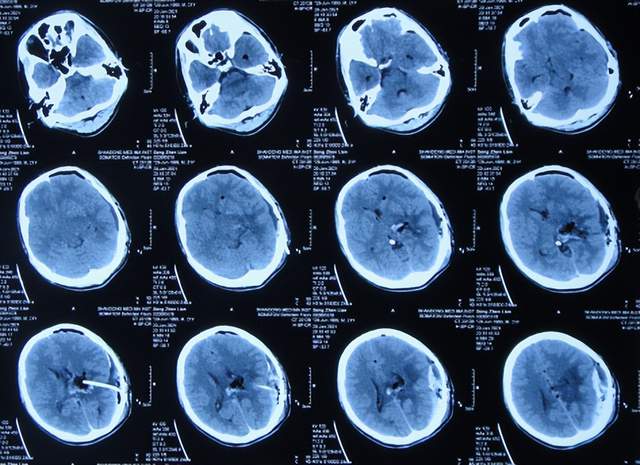

第2次出院后5个月即2022年6月初,再次出现头痛的症状,因左侧颞角再次增大,于2022年7月18日,第3次来到李小勇脑脊液科治疗。入院时:仅时有头痛。查头颅CT示左侧颞角扩张(图-33)。

图-33:2022年7月18日头颅CT

入院后3天即2022年7月21日,显微镜下颞角脉络丛切除术+分流管调整术,留置引流一根;术后查头颅CT示脑室内有2根管(图-34)。

图-34:2022年7月21日头颅CT

入院后11天即2022年7月29日(脉络丛切除术后8天),查头颅CT示引流术后状态(图-35)。

图-35:2022年7月29日头颅CT

入院治疗12天即2022年7月30日(脉络丛切除术后9天),给予拔除了原脑室腹腔分流管,查头颅CT示脑室内有一根管(图-36)。

图-36:2022年7月30日头颅CT

入院治疗21天即2022年8月8日(脉络丛切除术后18天),查头颅CT未见异常(图-37),患者身体无异常(图-38)。

图-37:2022年8月8日头颅CT

2022年8月22日(脉络丛切除术后32天),查头颅CT示颞角未见扩张(图-39),给予夹闭引流管。

图-39:2022年8月22日头颅CT

夹闭引流管14天后即2022年9月5日(脉络丛切除术后46天),查头颅CT示未见异常(图-40)。

图-40:2022年9月5日头颅CT

夹闭引流管15天后即2022年9月6日(脉络丛切除术后47天),给予拔除了脑室外引流管,当天查头颅CT示脑室基本正常(图-41);患者身体无异常。

图-41:2022年9月6日头颅CT

拔除了脑室外引流管后6天即2022年9月12日, 查头颅CT示未见异常(图-42);身体一切正常,于2022年9月16日出院。

图-42:2022年9月12日头颅CT

出院后3个月即2022年11月,在当地医院查头颅CT示无异常(图-43);本人叙述身体一切正常。

图-43:2022年11月头颅CT